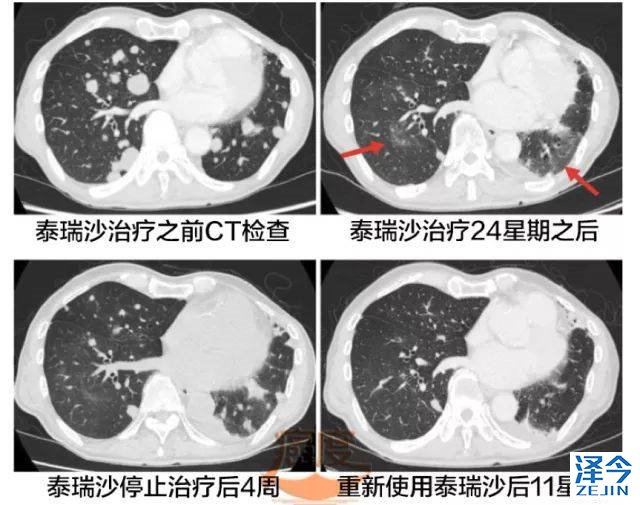

随着第十线的化疗结束之后,患者开始在2016年6月使用奥希替尼, 8周后病人进行全身CT和核磁检查,检查结果表明肺部病灶、脑转移灶急剧萎缩,使用奥希替尼24周(大概6个月),尽管全身的病灶仍在缩小,但是胸部CT显示肺下叶有两个无症状的磨玻璃影。

这个被认可可能是奥希替尼诱导的间质性肺炎(ILD),因此患者停止了使用奥希替尼。

停用奥希替尼四周之后,影像学检查显示病人双肺出现新的转移灶,但是病人肺部的毛玻璃阴影(GGO)只是轻度缓解。由于之前报道在奥希替尼治疗期间,出现这种频繁短暂的肺部不透明(TAPO),还是可以继续使用奥希替尼治疗。

重新使泰瑞沙4星期后,胸部CT揭示出肺部多发结节的萎缩,同时血浆的肺腺癌相关抗原KL-6水平显著下降,从之前的911U/ml下降到664U/ml。

重新使用泰瑞沙11星期之后,全身的CT检查显示多发肺部结节减少。肺部的毛玻璃样阴影没有加重。